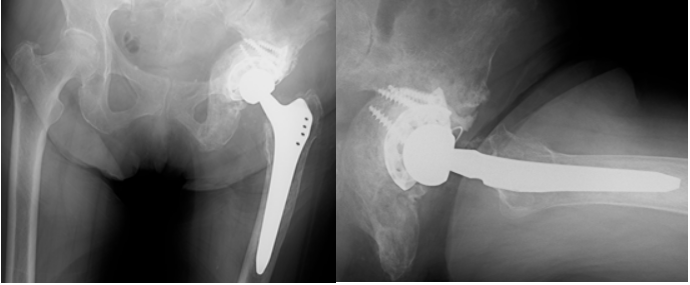

Because she remained free of hip symptoms, denosumab and radiation therapy were initiated. At 10 months postoperatively, radiographs showed increased sclerosis around the acetabular lesion (Fig. 8).

Figure 8: Radiograph at 10 months postoperatively demonstrating increased sclerosis around the metastatic acetabular lesion following adjuvant therapy.